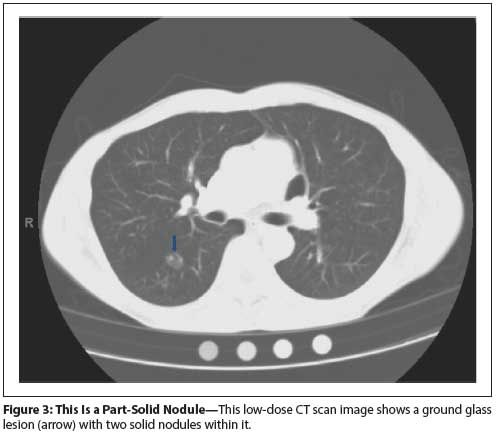

Figure 3: This Is a Part-Solid Nodule

Nonsolid or ground glass nodules (see Figures 1 and 2) are not very dense. Lung structures such as airways and blood vessels can be seen through them on CT scans.[8,21,22] Small ground glass lesions are difficult to biopsy and are not amenable to functional imaging. Ground glass lesions ≤ 10 mm are rarely cancerous. Ground glass lesions that persist over time are more likely to be malignant. Mixed lesions that have a solid component are more likely to be cancerous (see Figures 3 and 4).

The algorithm in Figure 4 outlines management in this setting.[20,34,35] A single solid or part solid pulmonary nodule < 6 mm in a person at high risk should be watched with annual low-dose CT. A solid or part-solid nodule 6 to 8 mm in size merits a repeat LDCT scan in 3 months and, if stable, again 3 months later. If it is growing, then it should be resected. If it is stable, then the patient should undergo LDCT screening annually. A nodule greater than 8 mm in size warrants evaluation with a PET/CT scan. Nodules that are of low suspicion after PET warrant repeat LDCT in 3 months and resection if there is growth. Those that have a PET result suspicious for cancer should be biopsied or resected.